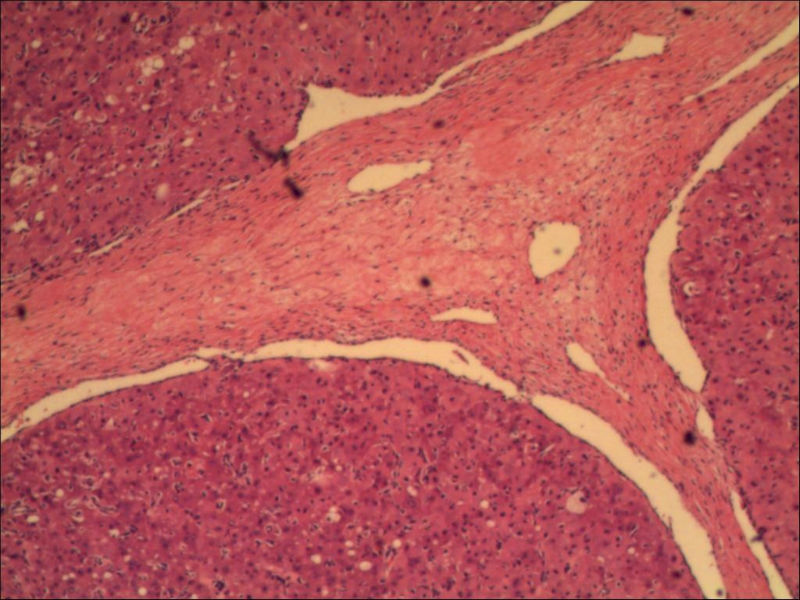

女,27岁,送检右侧卵巢肿物(另外还送检左侧卵巢肿物,大体及镜下显示为畸胎瘤),卵圆形,大小2×1×1cm,似有包膜。卵巢肿物图1

卵巢畸胎瘤中正常卵巢的黄体组织,铺砖样排列,胞浆宽大,较典型。

不好意思,可能是我没说清楚,患者对侧卵巢是畸胎瘤,不是同一侧的,我初步考虑门细胞瘤,图21,22,24,25,26中央的一些细胞是不是很像门细胞

谢谢大家的回答和解疑,忘记一个重要的病史,就是该女性为产妇。但是妊娠黄体瘤与类固醇细胞瘤怎么鉴别呢

那应该是妊娠黄体/黄体瘤,类固醇细胞瘤有嗜酸细胞和组织细胞样细胞两种,此例显然不是。